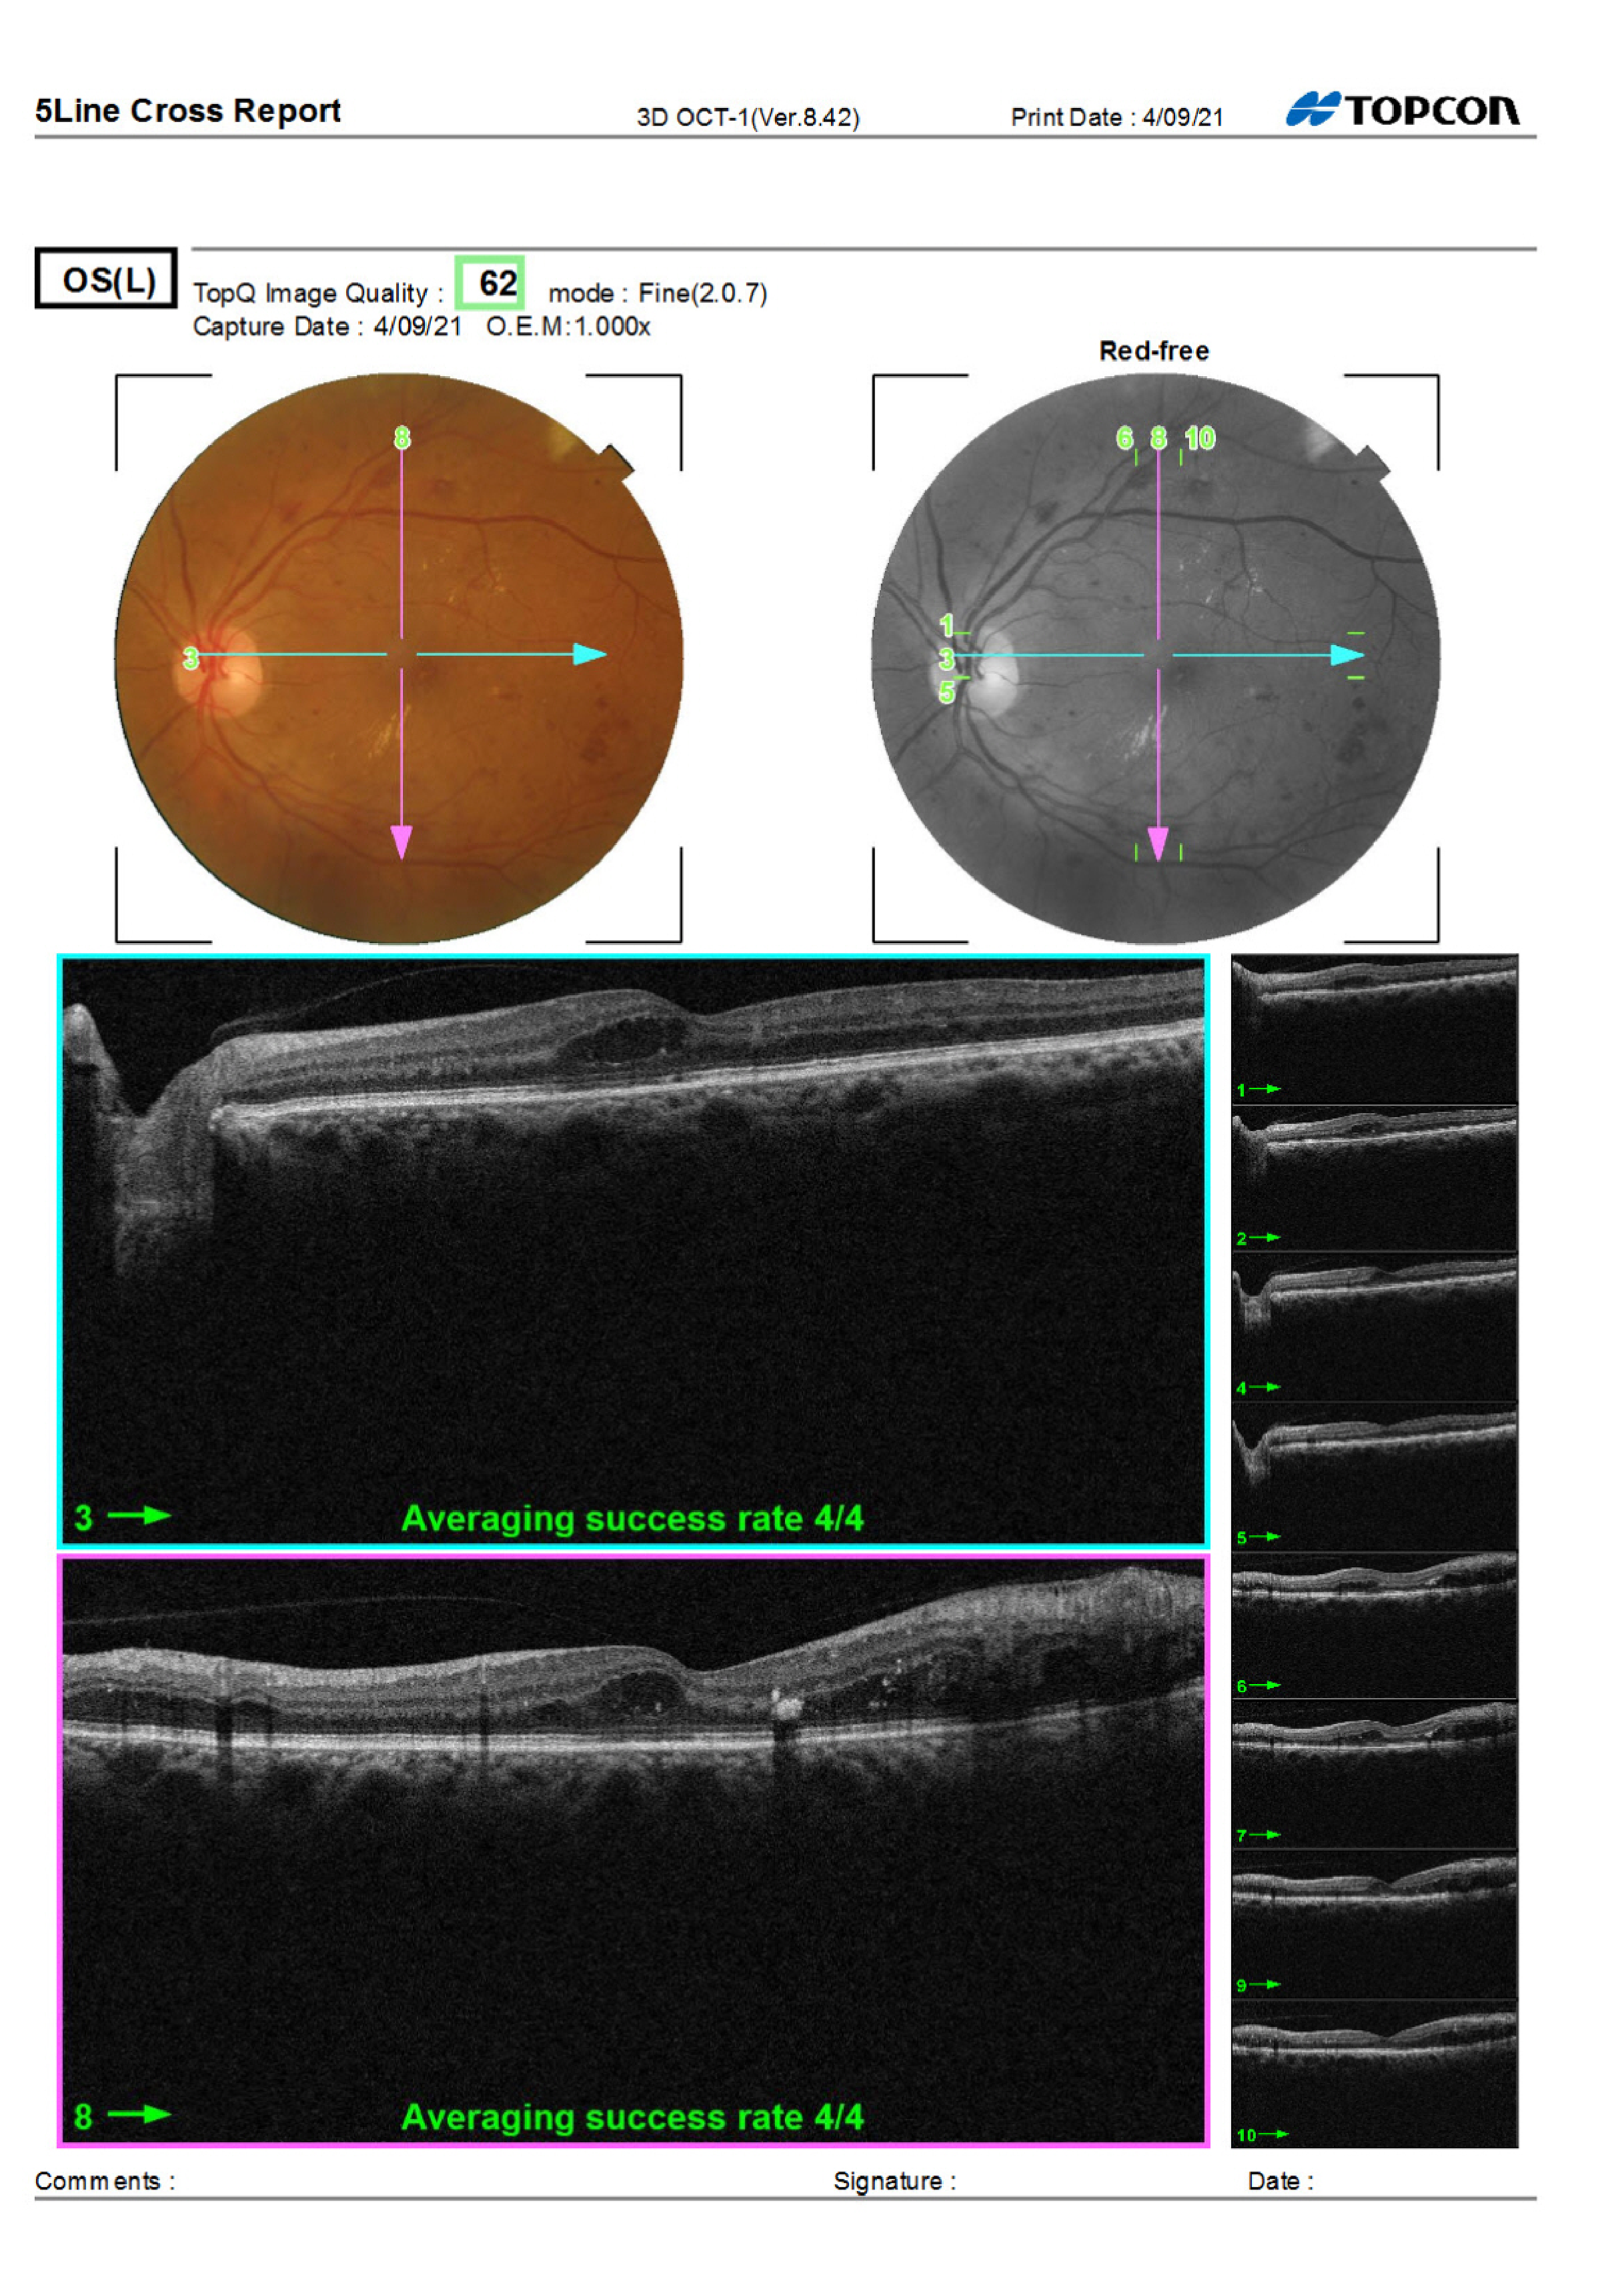

OS OCT Macula from Care1 case study.